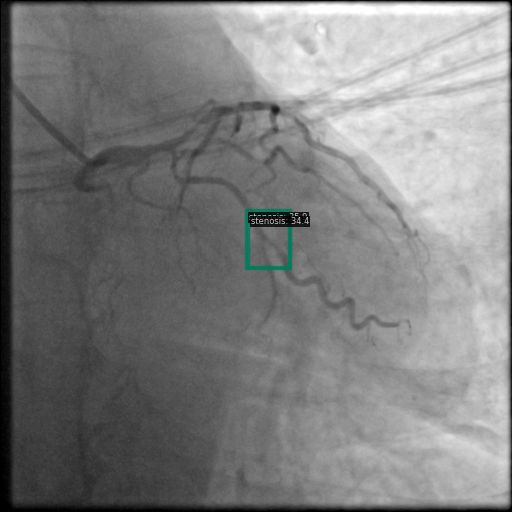

以下图像展示了每个模型在相同冠状动脉造影图像上的表现:

图5 DINO 的检测结果,结果更少但更精确。

3.1 DINO 检测模式

DINO 总体上检测结果较少,偶尔会错过相关的狭窄区域,但其检测到的区域通常都是准确的。这表明该模型学习了更严格的狭窄判断标准。例如,在某些测试案例中,DINO 以高置信度检测到单个狭窄区域,同时错过了更微妙的次要区域。这种模式在图 5 和图 8 中很明显,模型识别了主要狭窄区域但可能忽略了其他狭窄区域。

图8 DINO检测显示其倾向于更少、更精确的检测。